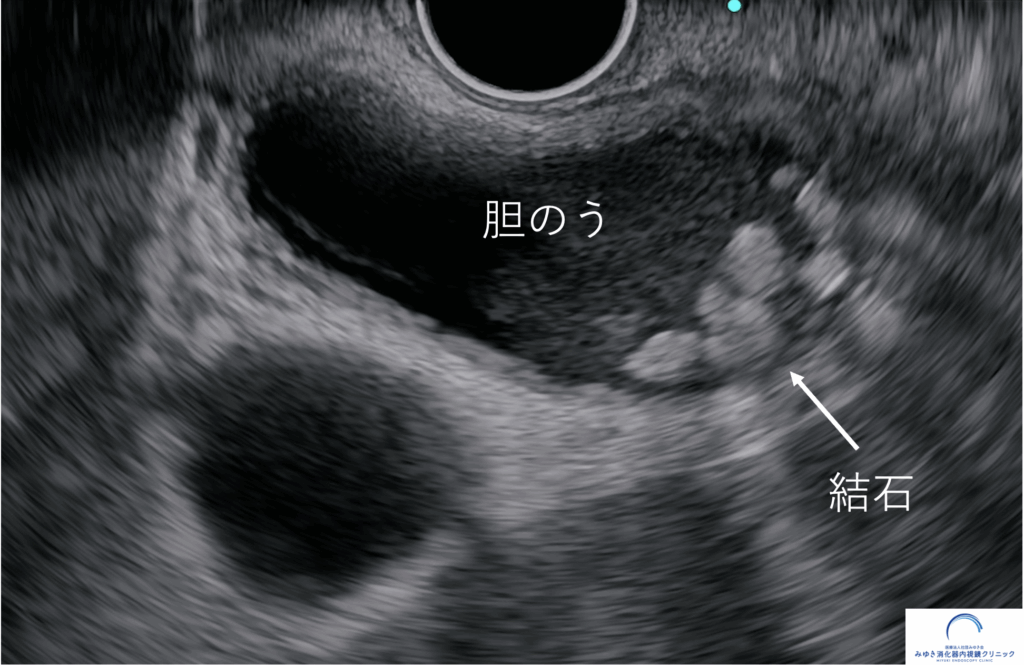

胆のう結石は手術すべき?

胆のう結石は手術が必要?無症状でも放置せず経過観察が重要です。手術を検討すべきサインや合併症リスクを専門医が解説。適切な対応の判断ポイントがわかります。

日本人の約10人に1人は、胆のうに結石があるといわれています。

人間ドックや健康診断の腹部エコー検査で「胆のう結石があります」と指摘され、驚いた経験のある方も多いのではないでしょうか。

胆のう結石は、肥満や生活習慣とも深く関係しており、近年は日本でも患者さんが増える傾向にあります。

胆のう結石は、症状がないからといってそのままでよいとは限らず、適切な経過観察と判断が大切です。

胆のう結石(たんのうけっせき)が見つかっても、多くの方は症状がありません。